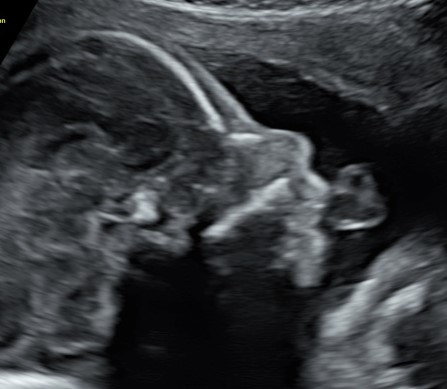

Il tesoro in ecografia è sempre più bello, infatti è da questo mese, ma soprattutto dal prossimo che comincerà ad ingrassare e diventare più tondetto per la gioia degli occhi di babbo e mamma!